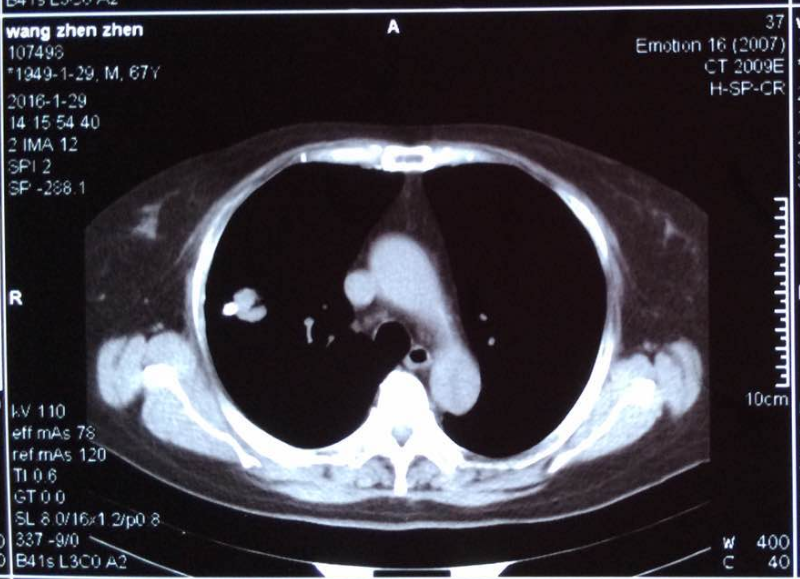

胸部影像病例讨论实录气管支气管肺篇病例43

肺瘢痕癌的影像学诊断(附11例分析)